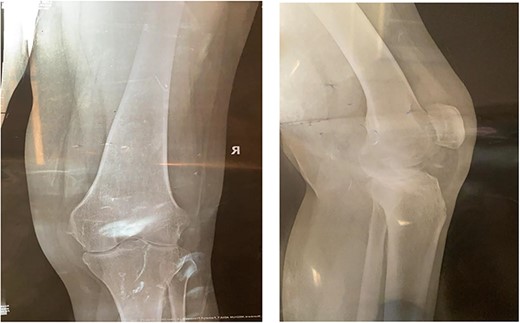

On the table, range of motion was 0–90°. Intraoperative image intensifier was used and demonstrated excellent position of the implant and the osteotomy site (Fig. 4).

The patient lost some of her range of motion (ROM) in the post-operative period even with extensive physiotherapy. On her 4-month follow up appointment; ROM was 10–80°, which she sustained afterward. Plain radiographs continued to show no new HO formation at 4 months (Fig. 5).

Intraoperative image intensifier demonstrated position of the implant, screw and the osteotomy site.

Knee X-rays at 4 months visit continued to show no new HO formation, and continuation of healing of the osteotomy.